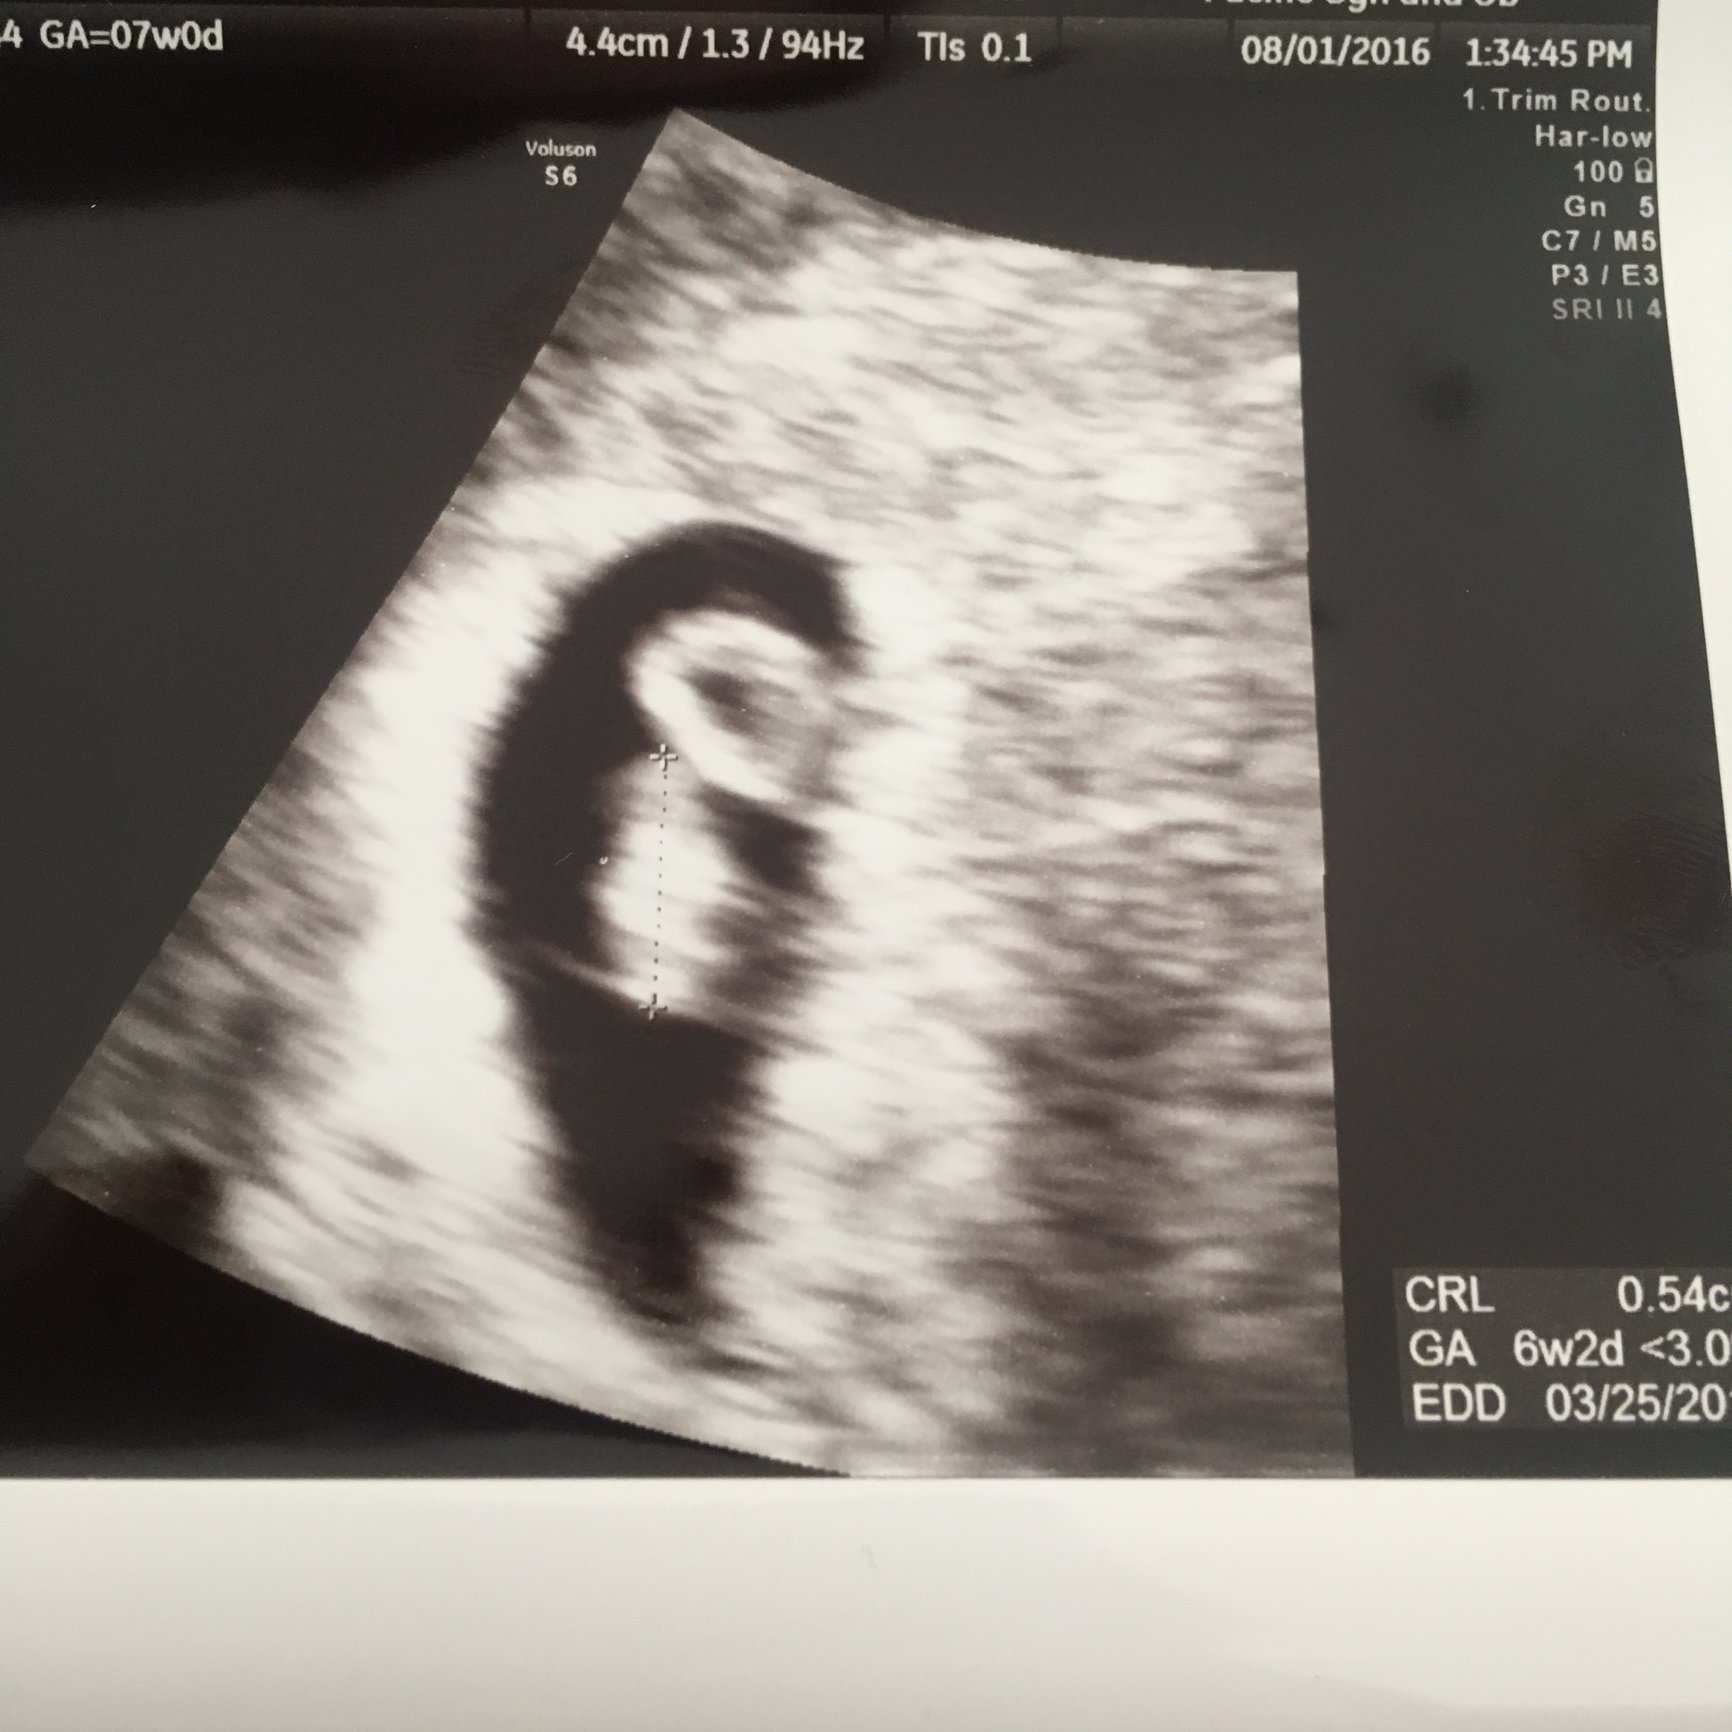

https://www.fertilityfriend.com/home/683816 BFP 6/30/16, MC 8/21/16 BFP 05/04/17, 5/10/17 Emergency LAP due to ectopic. Right tube removed. BFP 07/12/17, ECDD 03/25/18 - Silver Orion Born 3/23/18 BFP 09/30/19, EDD 06/11/20

BFP 07/12/17, ECDD 03/25/18 - Silver Orion Born 3/23/18